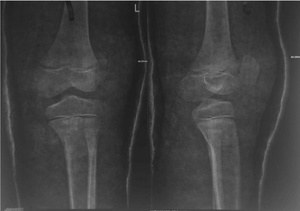

At the emergency room, radiographs were performed, which revealed a high-riding patella with a noticeable joint effusion as well as a small osteochondral fragment positioned distally to the patella. (Figure 2) As a result of the high-riding patella on the radiographs and the avulsion of the distal osteochondral side of the patella, a patellar sleeve fracture was detected. The surgery was scheduled for the next day.